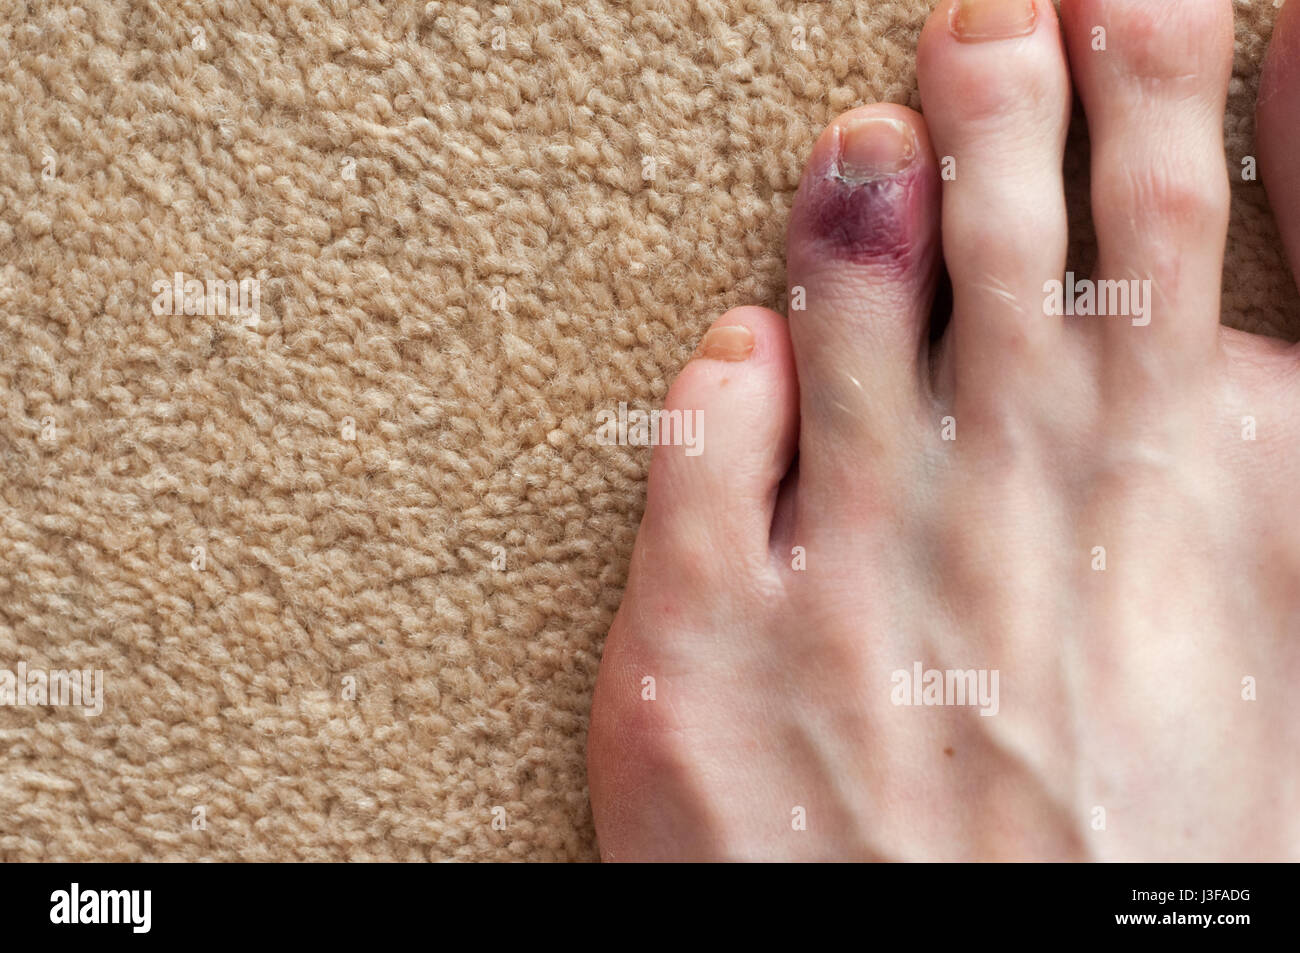

RF2FM8YC2–Blutergüsse an der kleinen Fußspitze. Nahaufnahme der gebrochenen kleinen Zehe eines älteren Mannes, der Verfärbungen zeigt.